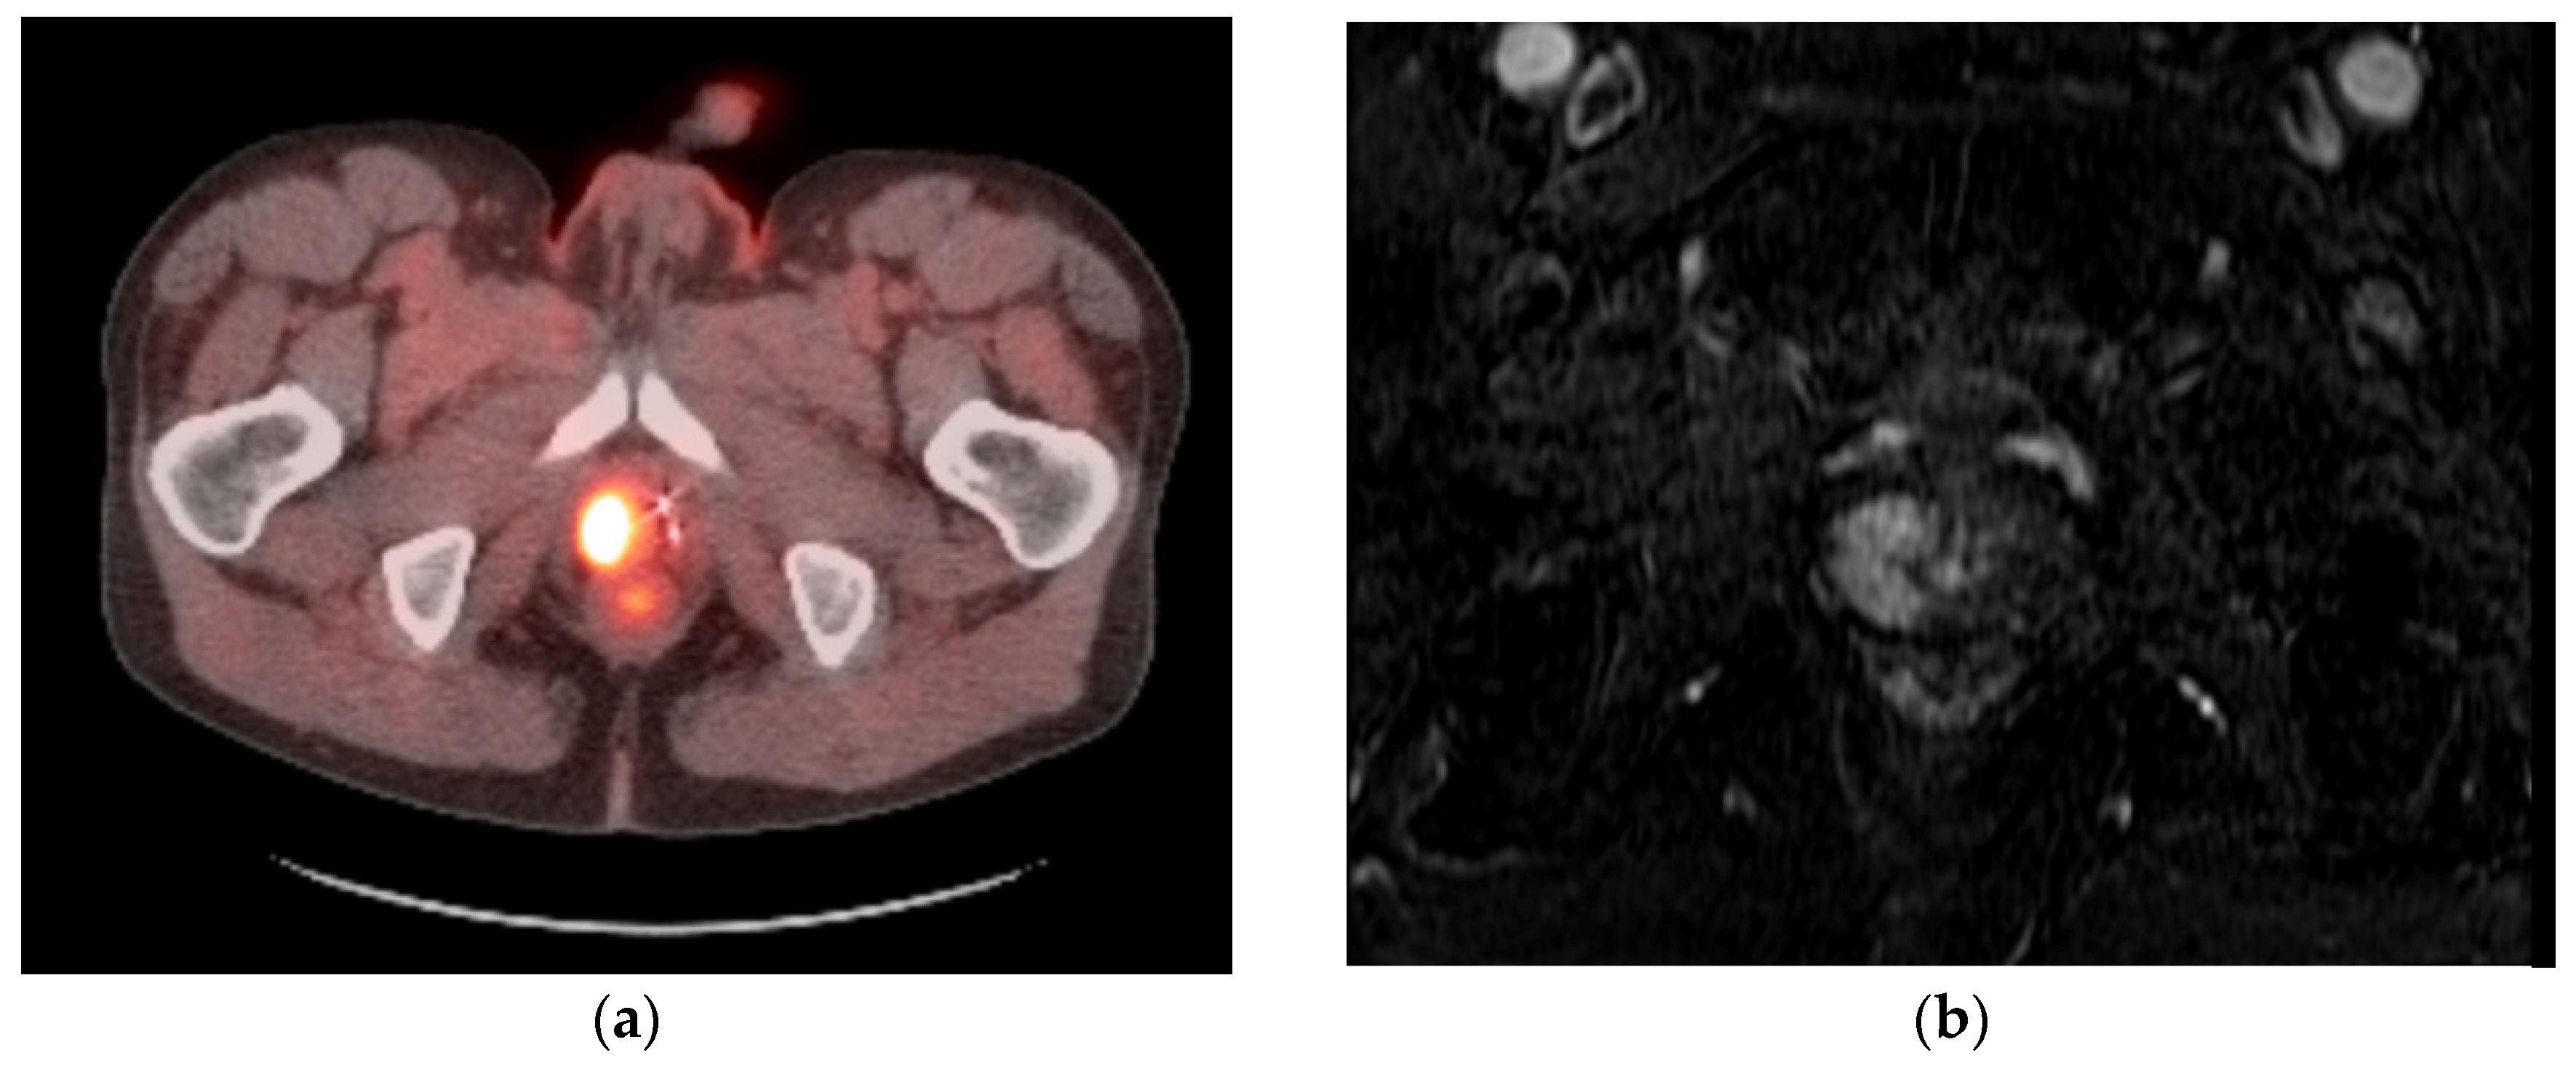

- Gangi, A.; Tsoumakidou, G.; Abdelli, O.; Buy, X.; de Mathelin, M.; Jacqmin, D.; Lang, H. Percutaneous MR-guided cryoablation of prostate cancer: Initial experience. Eur. Radiol. 2012, 22, 1829–1835. [Google Scholar] [CrossRef] [PubMed]

- Bomers, J.G.; Yakar, D.; Overduin, C.G.; Sedelaar, J.P.; Vergunst, H.; Barentsz, J.O.; de Lange, F.; Fütterer, J.J. MR imaging-guided focal cryoablation in patients with recurrent prostate cancer. Radiology 2013, 268, 451–460. [Google Scholar] [CrossRef]